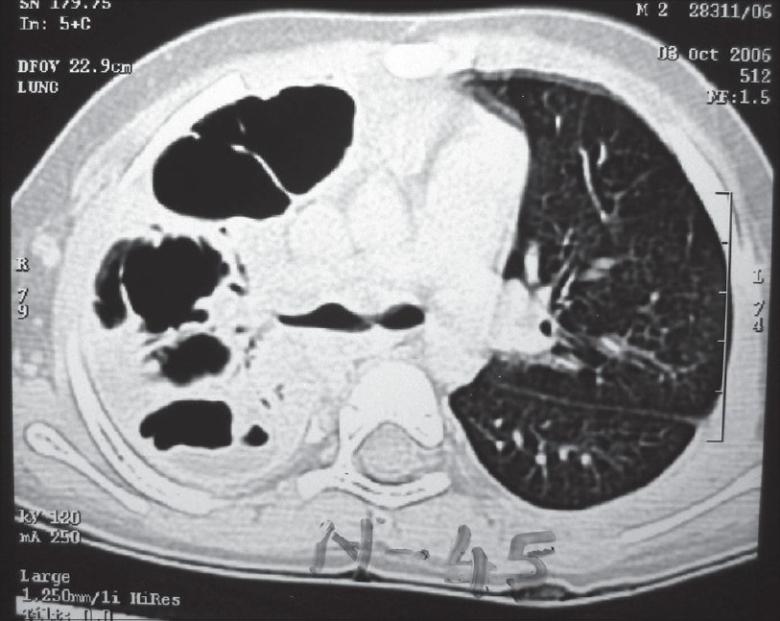

小儿脓胸:手术治疗

Empyema thoracis can produce significant morbidity in children if inadequately treated. Correct evaluation of the stage of the disease, the clinical condition of the child and proper assessment of the response to conservative treatment is crucial in deciding the mode of further surgical intervention. This ranges from intercostal chest tube drainage and video-assisted thoracoscopic surgery to open decortication. Surgical decortication becomes mandatory in neglected cases; it gives very gratifying results ameliorating the disease rapidly and is well tolerated by young patients. This article reviews the current literature and discusses the important considerations while managing these patients. Indications for surgery are highlighted, based on our large experience at a tertiary care center.

如果治疗不当,小儿脓胸可导致严重的发病情况。正确评估疾病阶段、患儿临床状况以及对保守治疗反应的恰当评估,对于决定进一步手术干预方式至关重要。这包括肋间胸腔闭式引流、电视辅助胸腔镜手术以及开胸纤维板剥脱术。在被忽视的病例中,手术纤维板剥脱术成为必要手段;它能迅速改善病情,取得非常令人满意的效果,且年轻患者耐受性良好。本文回顾了当前文献,并讨论了管理这些患者时的重要注意事项。基于我们在三级医疗中心的丰富经验,突出了手术适应症。